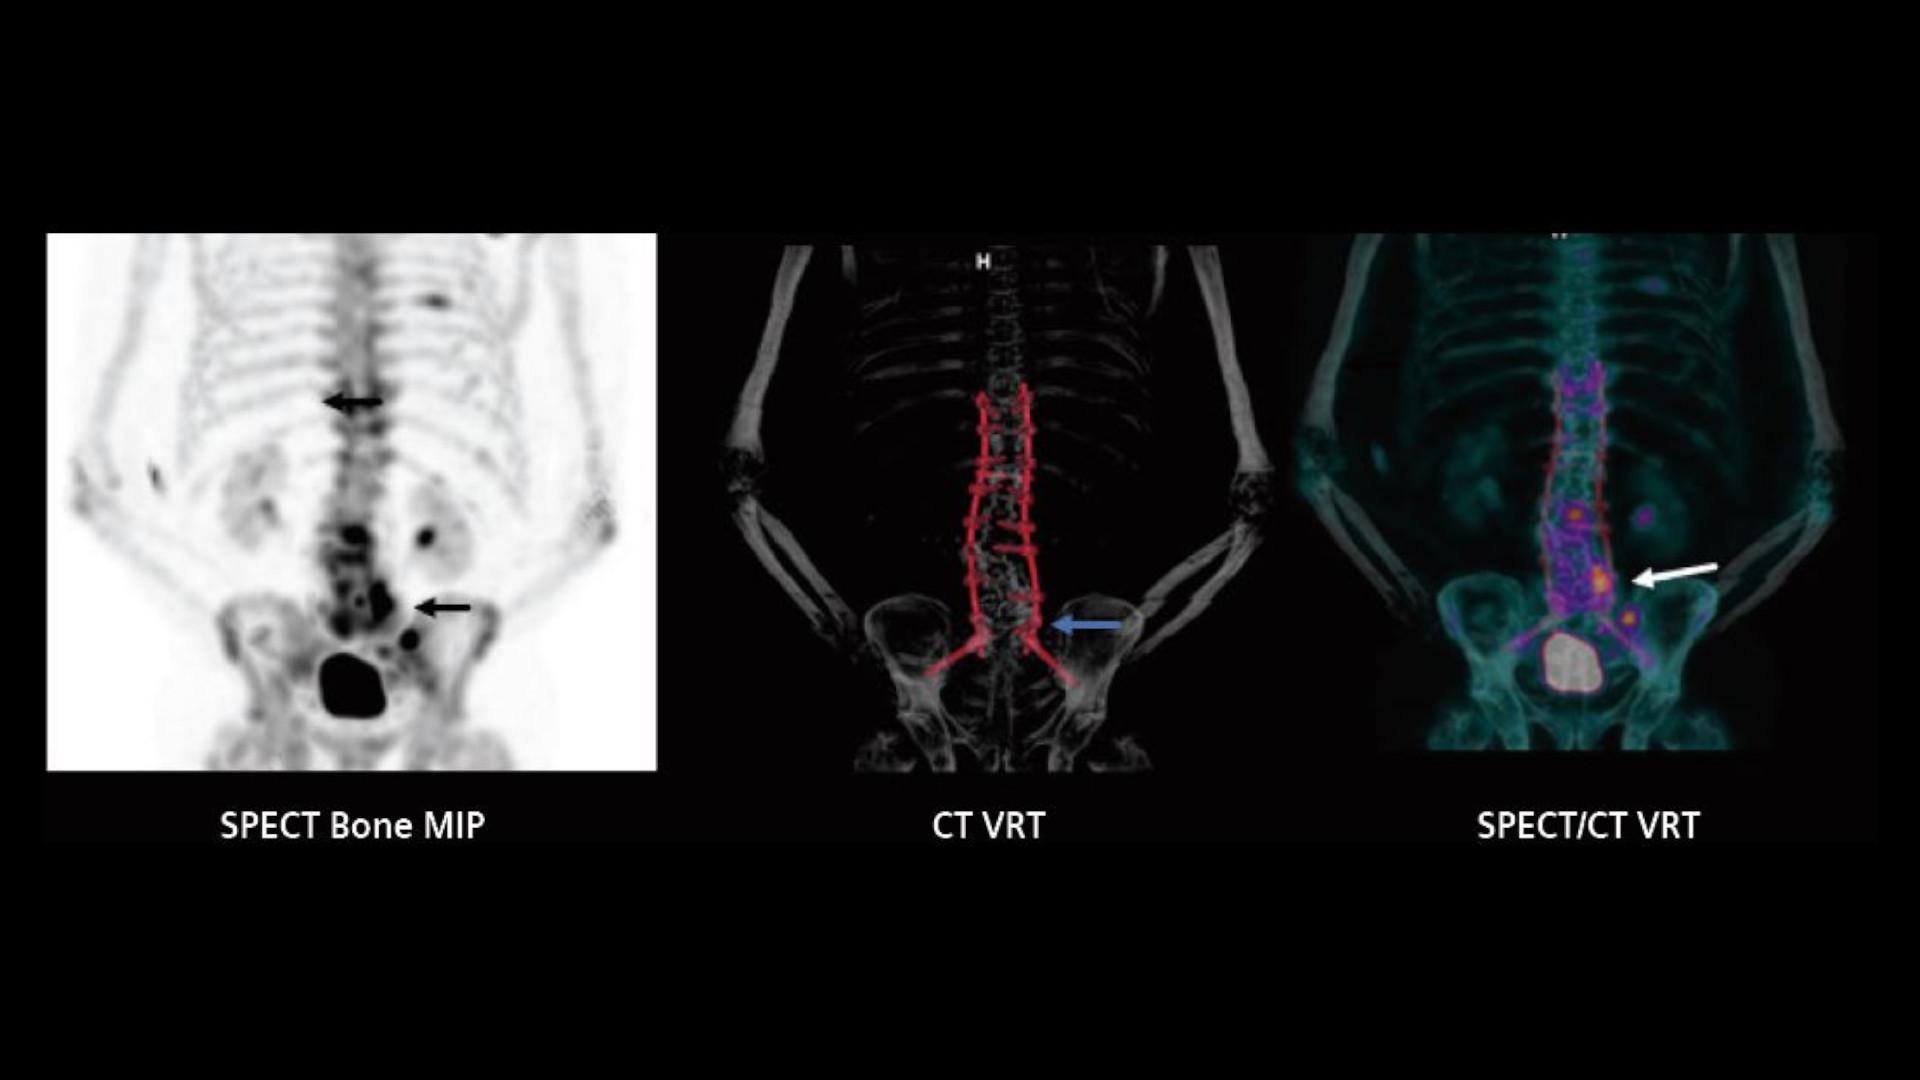

SPECT/CT imaging in the evaluation of pain following spinal fusion What Is A Spect Ct A single photon emission computed tomography (spect) scan is an imaging test that shows how blood flows to tissues and organs. Find out what to expect during your spect. It allows the clinician to assess the. What Is A Spect Ct.

SPECT/CT imaging in the evaluation of pain following spinal fusion What Is A Spect Ct Find out what to expect during your spect. A single photon emission computed tomography (spect) scan is an imaging test that shows how blood flows to tissues and organs. It allows the clinician to assess the. What Is A Spect Ct.